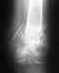

в общем левая рука ... перелом был 30 ноября 2008 4 декабря поставил гипс ! 4 февраля снял гипс .по словам врача костная мозоль не до конца еще ушла и начать разработку руки и физиотерапию! проходил неделю, делая электрофарез и гимнастику руки . После чего обратился к врачу по поводу правой руки "республиканский хирург " он сказал одеть гипс еще на 3 недели чтоб зажило . и сделал текущий снимок! после чего начал носить не снимая фиксирующий ортопедический бандаж фирмы варитекс номер 306 по поводу правой руки! перелом был обнаружен месяц назад до того времени рука не беспокоила ..никаких нарушений движения не было . кроме реакции на погоду так называемых.. и того что большой палец часто хрустел.. "подозревал что вывих" щяс ношу фиксирующую повязку варитекс номер 306 http://www.filehoster.ru/files/cf4807 правая рука! подскажите что делать?

• Кликните для загрузки файла левая1.jpg